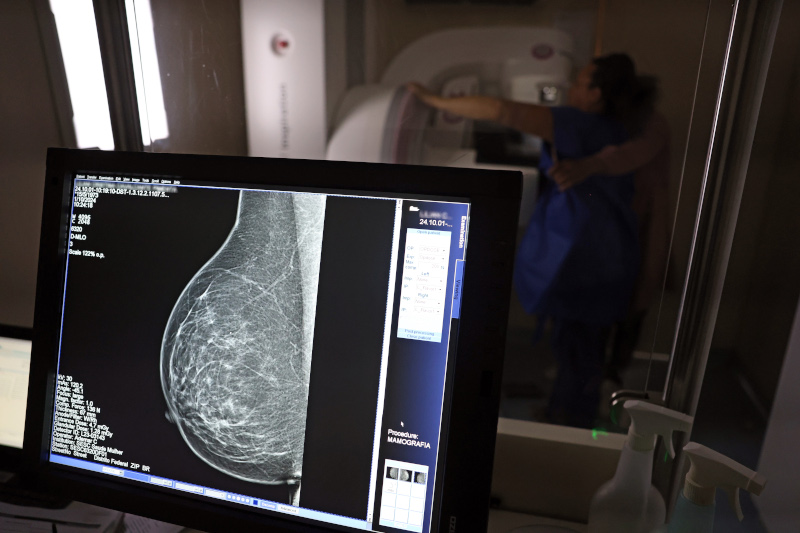

Dor e desigualdade na mamografia

No caso do câncer de mama, o estudo ouviu 170 mulheres de 50 a 69 anos, também frequentadoras das mesmas unidades básicas de saúde. O levantamento mostrou que 84% fizeram mamografia nos últimos cinco anos, mas elas também relataram barreiras importantes que atrapalham na adesão. A dor durante o exame apareceu como a principal barreira e foi citada por 59% das entrevistadas, seguida da longa espera para realizar a mamografia (44%), da dificuldade para agendar (40%) e do medo do diagnóstico (32%).

“A dor aparece como o principal obstáculo. Isso indica que experiências negativas prévias têm um impacto duradouro, influenciando se a mulher vai repetir ou evitar o exame. Portanto, o que mais me chamou atenção foi a dor como barreira mais citada”, afirma Alice Barros Câmara, pesquisadora da Fosp e autora desta pesquisa. “Muitas vezes, os estudos enfatizam custos, distância, falta de informação ou medo do resultado. Mas a experiência física da dor, sendo a mais relatada, sugere que não basta só estruturar o sistema, é necessário melhorar a experiência da usuária”, continua.